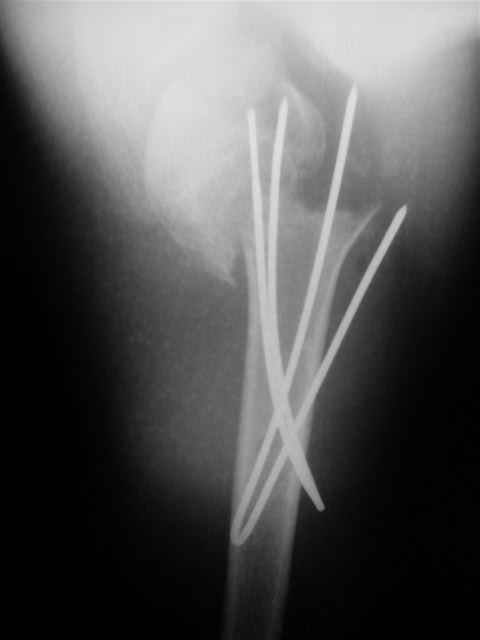

Спасибо за участие в дискуссии -перелом шейки плеча, для себя я прояснил многие технические моменты...

Посылаю послеоперационные Рг граммы.

Поздравляю, получилось просто замечательно. Если можно, расскажи чуть подробнее, как делали - как вправляли, как вводили спицы, поворачивали ли их?

|

Спасибо за поздравления:-))

Я и сам доволен результатом. В предпоследнем письме я кратко описал ход операции - закрыто репонировать не удалось( 2 недели с момента травмы и 1 неделя после неудачной репозиции) после удаления пучков спиц, пришлось сделать - 2см разрез на уровне перелома и с помощью периостального элеватора (золотое правило механики) *одеть* головку на дистальный отломок.

Спицы проводил через старые отверстия, вращая пучок импактором- направителем при его введении в головку.